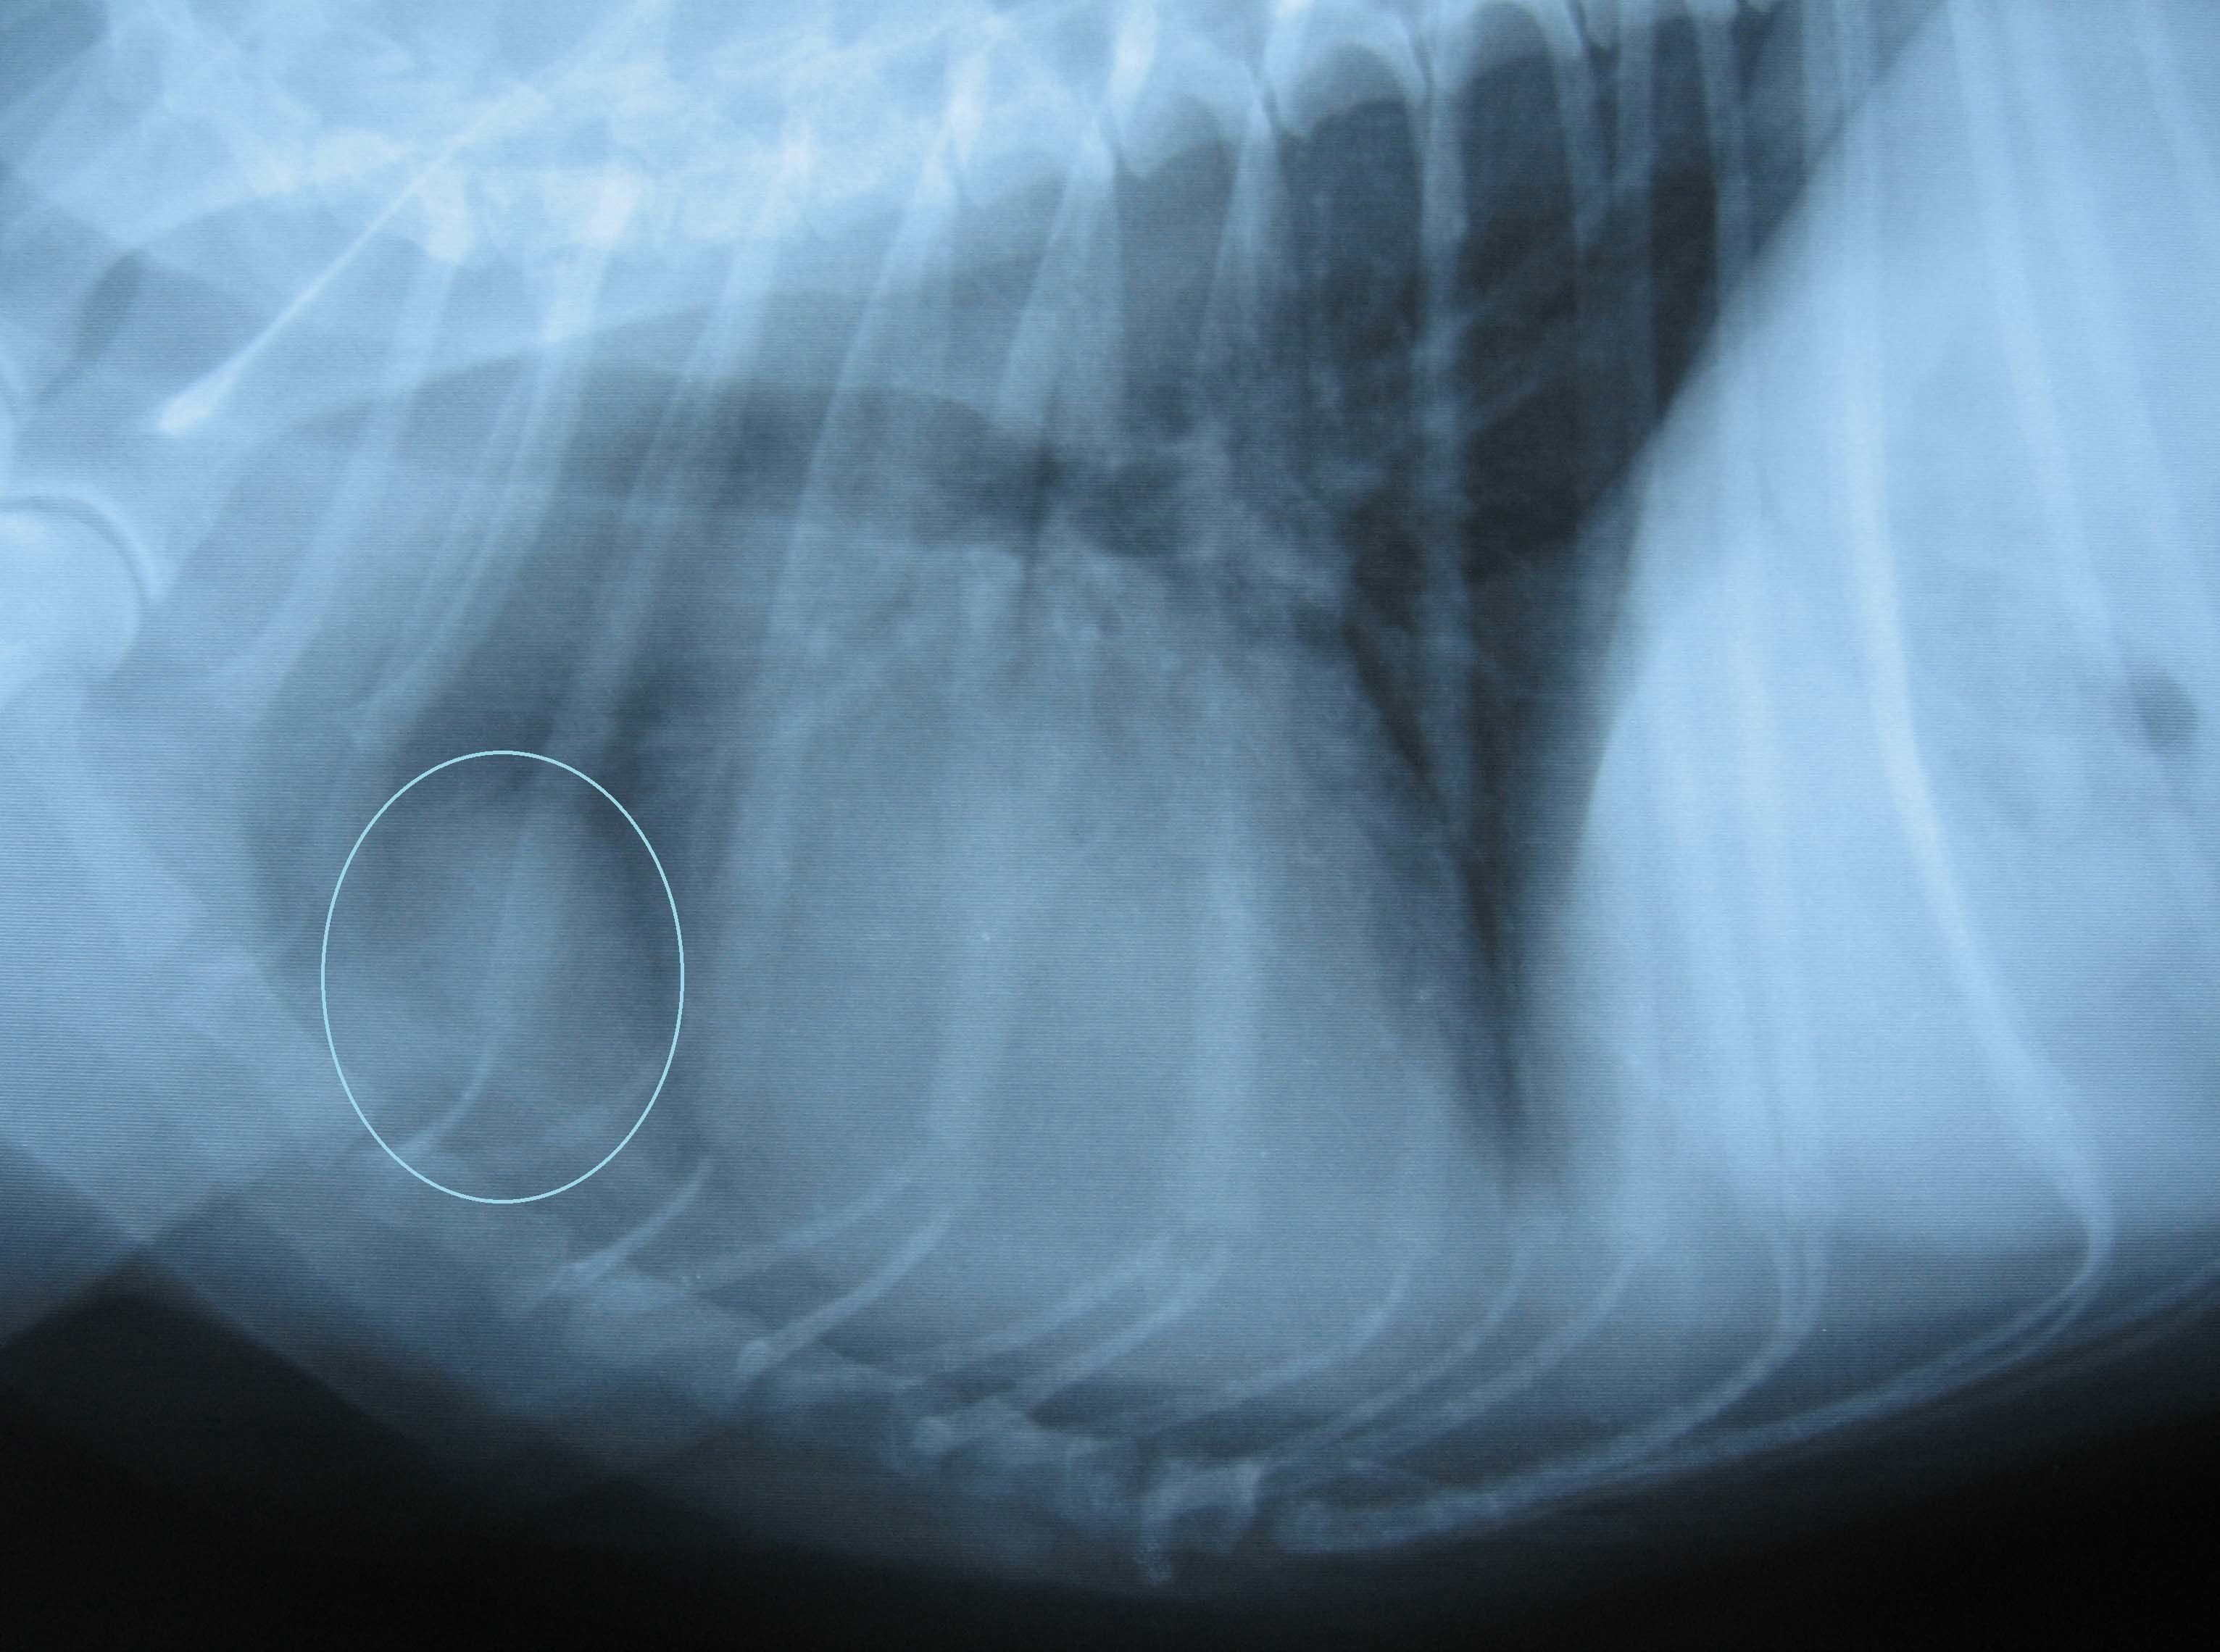

胸腔内の腫瘍

胸腔は体内のうち、胸の部分にある空間のことで、心臓や肺などが収まっています。この部分にできる腫瘍には、縦郭(じゅうかく)腫瘍などさまざまな種類があります。いずれも、皮膚の腫瘍のように見てわかるものではなく、犬も痛がったりしないため、飼い主さんが気づくのは困難。見てわかる症状が出てきたときにはかなり進行している場合が多いです。

胸腔内腫瘍のレントゲン写真。白マルで囲まれた部分が腫瘍部分です。